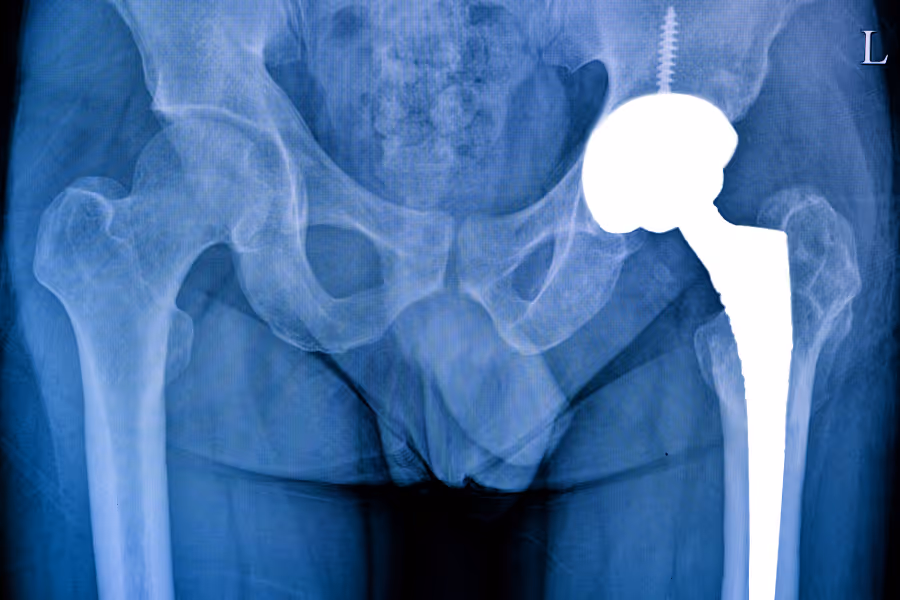

- X-Rays: Simple images check if the implant is sitting correctly and if the bone looks healthy.